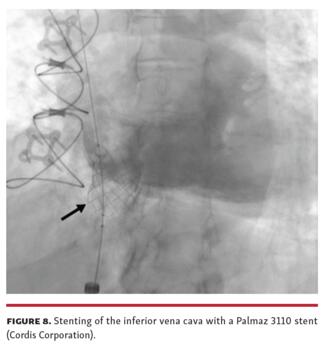

IVC stenosis is a rare complication of bicaval orthotopic heart transplant. IVC stenosis can occur at either the cavoatrial anastomosis or the caval cannulation site, with presentations ranging from acute shock early post transplant to a more indolent course. Causes include extensive hemostatic suturing, fibrous contraction, and donor-recipient size mismatch. Treatment strategies include percutaneous balloon angioplasty (Figure 7), stenting (Figure 8), and surgical revision. Evaluating for IVC stenosis is recommended for unexplained lower extremity edema, new-onset ascites, or liver abnormalities after bicaval heart transplant.